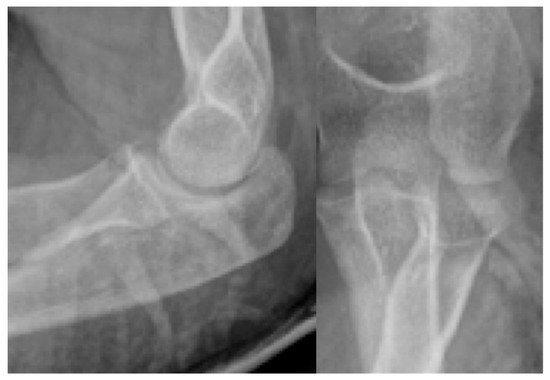

We investigated whether interrater reliabilities of the AO/OTA classification of patellar fracture change with the imaging modalities applied, including plain radiography and two- and three-dimensional (2-D and 3-D) computed tomography (CT). Seven orthopedic specialists and four orthopedic residents completed a survey of 50 [...] Read more.

We investigated whether interrater reliabilities of the AO/OTA classification of patellar fracture change with the imaging modalities applied, including plain radiography and two- and three-dimensional (2-D and 3-D) computed tomography (CT). Seven orthopedic specialists and four orthopedic residents completed a survey of 50 patellar fractures to classify the fractures according to the AO/OTA classification for patellar fractures. Initially, the survey was conducted using plain radiography only, then with 2-D CT introduced three weeks later and 3-D CT introduced six weeks later. Fleiss’ Kappa coefficients were calculated to determine interrater reliability. The overall interrater reliability of the AO/OTA classifications was 0.40 (95% CI, 0.38–0.42) with plain radiography only and 0.43 (95% CI, 0.41–0.45) with the addition of 2-D CT. With the addition of 3-D CT, the reliability was significantly improved to 0.54 (95% CI, 0.52–0.56). In specialists, interrater reliability of the classifications was moderate with all three imaging modalities. With the use of 3-D CT, interrater reliability of the classification was 0.53 (95% CI, 0.50–0.56), which was significantly higher than that with the use of 2-D CT (κ = 0.45; 95% CI, 0.42–0.48). In residents, interrater reliability of the classification was 0.30 (95% CI, 0.24–0.36) with plain radiography. The reliability improved to 0.49 (95% CI, 0.43–0.56) with the addition of 2-D CT, which was significantly higher than that with plain radiography only. The use of 3-D CT imaging improved interrater reliability of the classification. Therefore, surgeons, especially residents, may benefit from using 3-D CT imaging for classifying and planning the treatment of patellar fractures. Full article

Show Figures

Figure 1